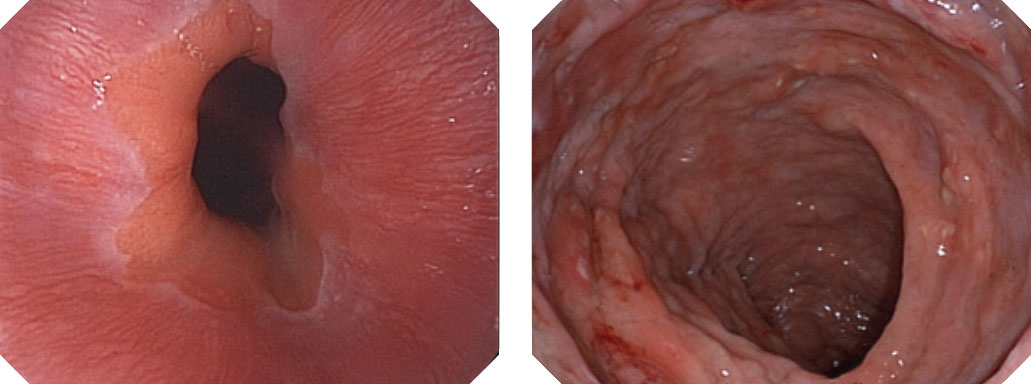

百万级像素高清传感器,1080P全高清视频信号输出,图像清晰。

白光图像

白光图像

SFI图像

SFI图像